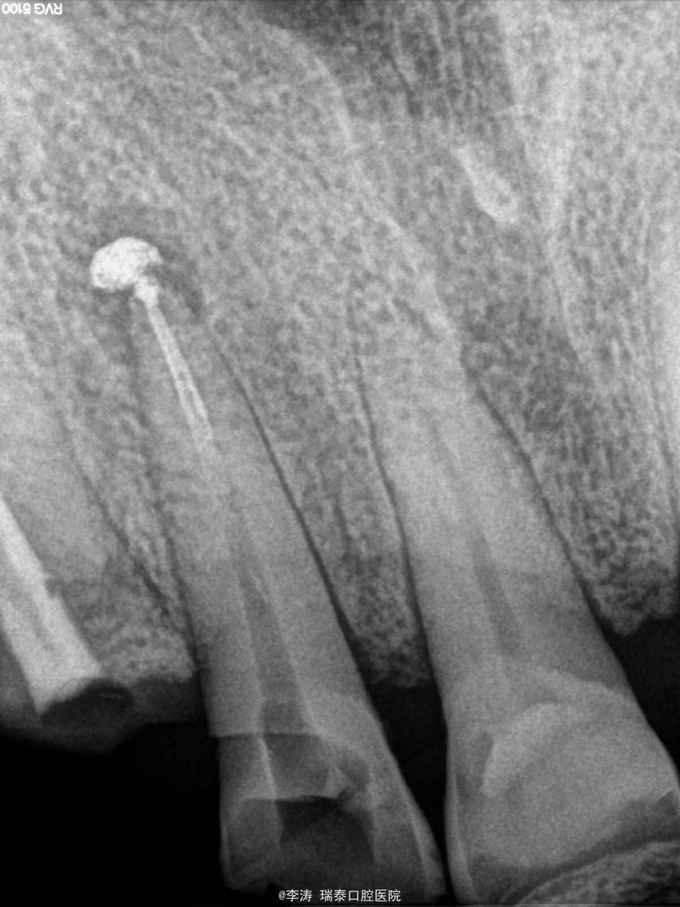

右上前牙疼痛不适1周,自诉半年前曾行根管治疗

13叩+,松-,x线片示13牙根尖暗影,根尖部有约1mm高密度影像,根管内充填影像

怀疑超充引起根尖炎症,建议行根管再治疗或者根尖切除术。患者选择先保守治疗,遂开髓。 术中根管内未见牙胶尖,大量vita糊剂充填于根管,遂行vita糊剂去除,拟行常规根管再治疗术。

1,术前病史和详细检查很重要,要是病人直接选择根尖切除术,我可能真的是百口莫辩。但这种情况真的是防不胜防,只能自求多福吧 2,超充的vita糊剂很难去除,可能做了再治疗后还是得采取根尖手术,不知道大家对去除超充糊剂有什么建议 3,充vita糊剂半年就发生了炎症,这也是我不太明白的,可能是根管预备消毒没做好,也可能是vita糊剂的效果还有待观察。